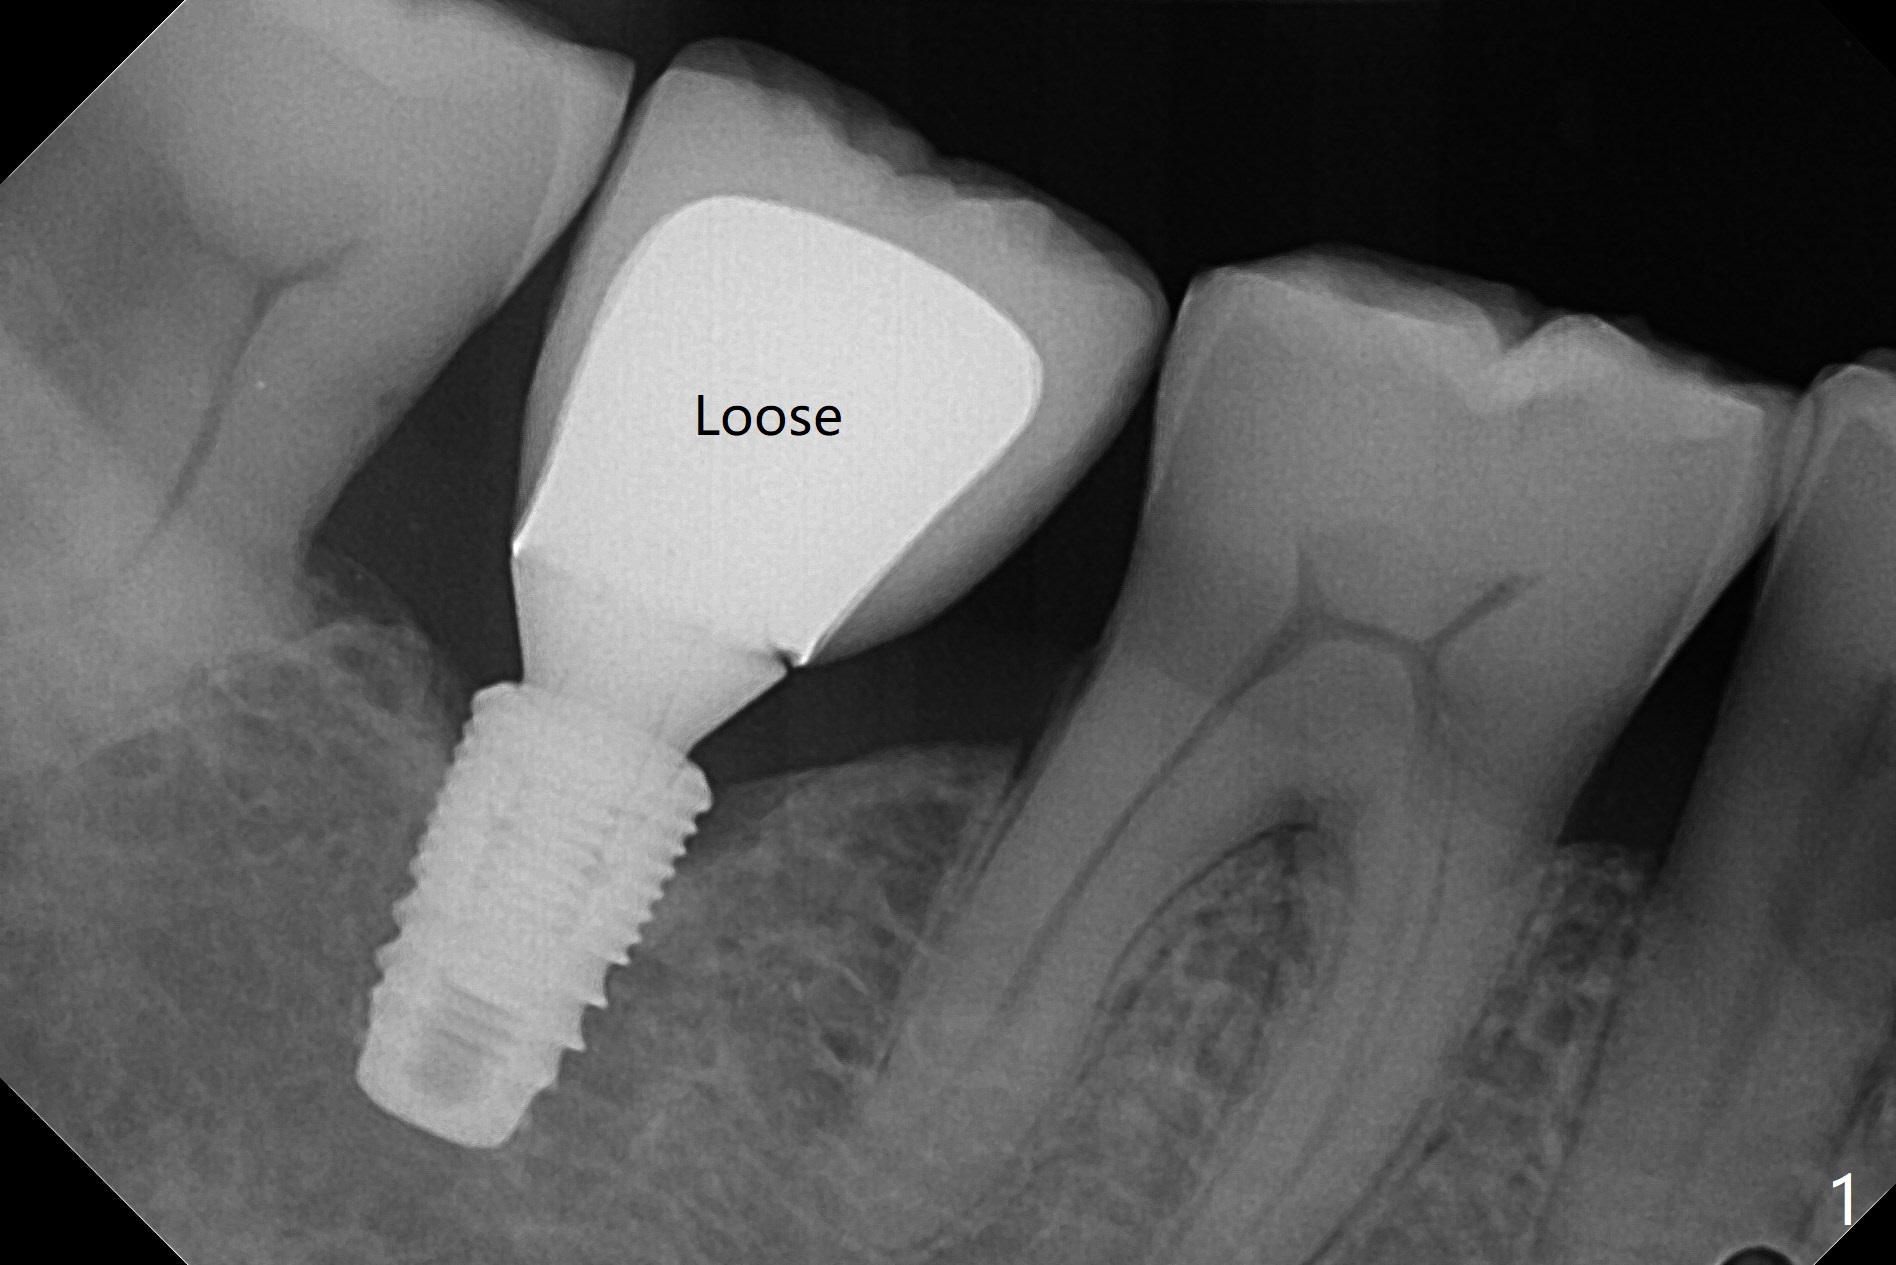

74岁男, 为何松动?

植体与基台交界处第一部分有间隙,没有骨阻挡。

如何诊断处理     Last     Next     分类